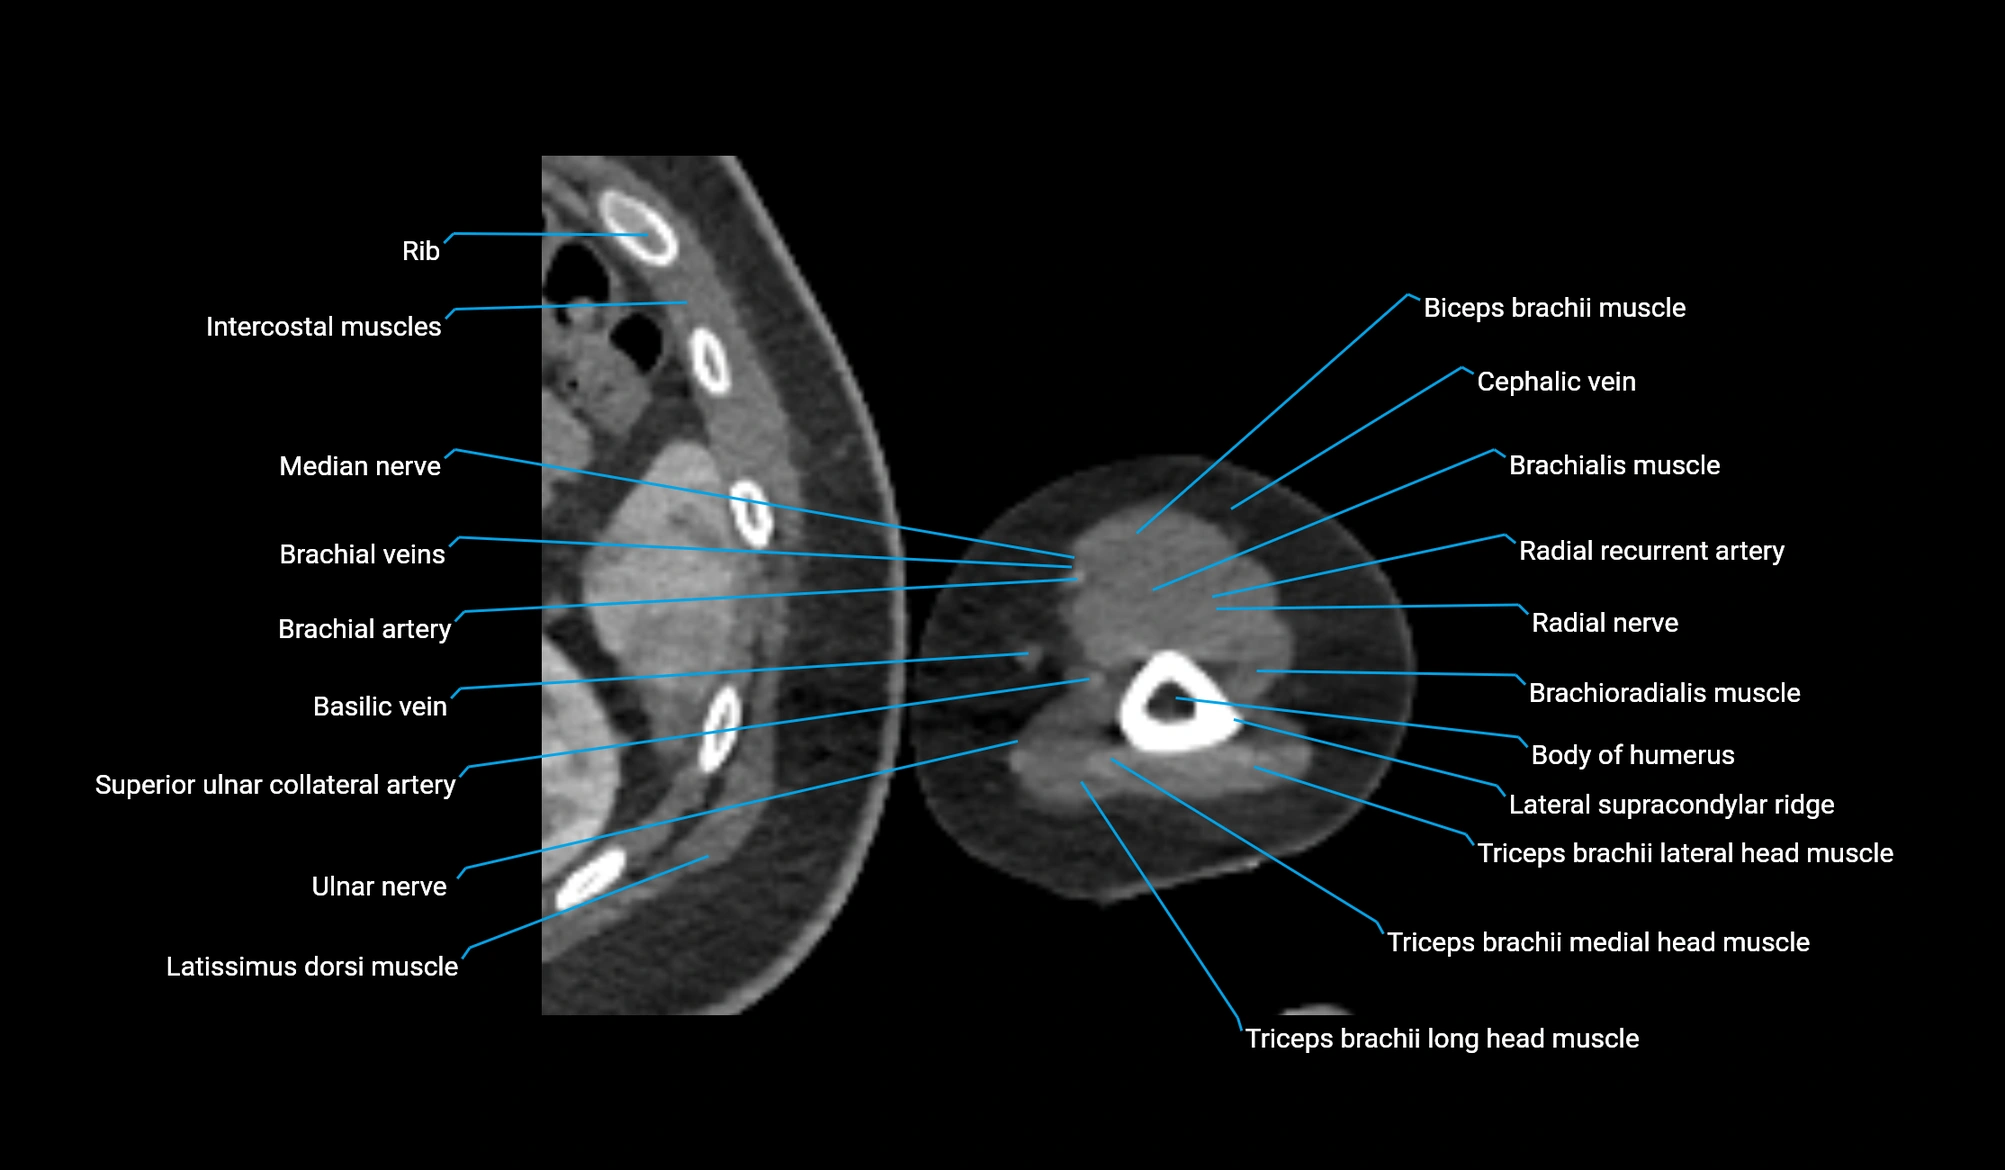

- Basilic vein

- Brachial artery

- Brachialis muscle

- Brachioradialis muscle

- Lateral supracondylar ridge

- Long head of triceps brachii muscle

- Medial head of triceps brachii muscle

- Median nerve

- Radial nerve

- Radial recurrent artery

- Superior ulnar collateral artery

- Ulnar nerve